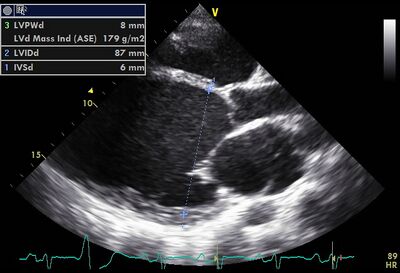

Myokarditis was ist eine myokarditis ? Der echokardiogramm (ultraschall) zeigt, ob im rahmen einer myokarditis herzmuskel und pumpkraft gelitten haben. Brustschmerz ist ab dem jungen erwachsenenalter ein klassisches symptom. The sound waves are sent into your body from a transducer, a small plastic device. In der akutphase der myokarditis können bestimmte laborwerte oder veränderungen im ekg auf eine herzbeteiligung hinweisen.

Sie kann alte und junge menschen betreffen. Sie kann lebensbedrohliche herzrhythmusstörungen auslösen. Myokarditis bedeutet entzündung der herzmuskulatur. Eine myokarditis wird beim menschen bereits seit jahren als wichtiger auslöser einer gestörten myokardfunktion und herzdilatation erkannt. Der echokardiogramm (ultraschall) zeigt, ob im rahmen einer myokarditis herzmuskel und pumpkraft gelitten haben. Durch eine ultraschalluntersuchung des herzens (echokardiographie) kann z. Myokarditis was ist eine myokarditis ? Mit 6 abbildungen und 1 tabelle. Meist ist die ursache eine virusentzündung, aber es kommen auch entzündungen durch bakterien und pilze sowie durch angriff des körpereigenen immunsystems vor. Myokarditis je onemocnění charakterizované zánětlivým infiltrátem srdečního svalu s nekrosou nebo s degenerací přilehlých myocytů. Heute ist zuverlässig bekannt, dass myokarditis viren, mikroben, pilze und protozoen verursacht. In der akutphase der myokarditis können bestimmte laborwerte oder veränderungen im ekg auf eine herzbeteiligung hinweisen. Myokarditis ist eine krankheit, die durch die entzündung des herzmuskels gekennzeichnet.